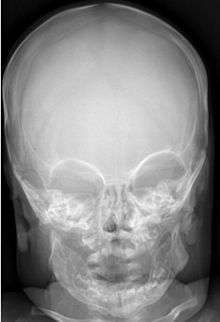

Most infants with infantile cortical hyperostosis are diagnosed by physical examination. X-rays can confirm the presence of bone changes and soft tissue swelling. Biopsy of the affected areas can confirm the presence of typical histopathological changes. No specific blood tests exist, but tests such as erythrocyte sedimentation rate (ESR) and alkaline phosphatase levels are often elevated. A complete blood count may show anemia (low red blood cell count) and leukocytosis (high white blood cell count). Other tests may be done to help exclude other diagnoses. Ultrasound imaging can help diagnose prenatal cases.

Radiographs initially show layers of periosteal new bone formation with cortical thickening. Periosteal new bone may cover the diaphysis of the bone, causing an increase in diameter of the bone. Over time, the periosteal new bone density increases, becoming homogenous with the underlying cortex. Eventually the bone remodels and resumes a normal appearance.